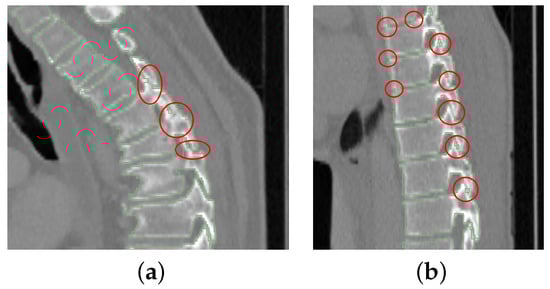

5. Discussion

5.1. Segmentation Performance

5.2. Current Limitations and Future Work